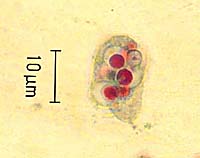

Entamoeba gingivalis có lớp bào tương bên ngoài có thể phân biệt được với lớp bào tương ở bên trong, trung thể thường ở giữa nhân. Trong nguyên sinh chất có chứa nhiều vi khuẩn và nhân bạch cầu. Chúng có kích thước từ 8 đến 15 µm. Phân tích bệnh phẩm trong miệng của những người bị bệnh viêm răng lợi thường phát hiện thấy loại amíp Entamoeba gingivalis hiện diện.

Theo nghiên cứu của một số nhà khoa học, tỷ lệ nhiễm Entamoeba gingivalis chiếm 90,77% ở bệnh nhân bị sâu răng; 99% ở bệnh nhân bị viêm quanh răng; 62,5% ở bệnh nhân bị viêm lợi... Entamoeba gingivalis ăn các vi khuẩn, bạch cầu, các tế bào thoái hóa; có khi thấy cả hồng cầu. Vai trò gây bệnh của loại amíp Entamoeba gingivalis hiện nay đang có nhiều ý kiến trái ngược nhau. Đa số các nhà khoa học cho rằng Entamoeba gingivalis không gây bệnh, sự có mặt của loại amíp này được phát hiện trong các bệnh răng miệng chỉ là hiện tượng cộng sinh với loại vi khuẩn Staphylococcus. Trái lại, một số nhà khoa học khác lại cho rằng amíp Entamoeba gingivalis có liên quan đến một số bệnh về răng miệng. Ở Việt Nam, theo số liệu điều tra của Viện Sốt rét-Ký sinh trùng-Côn trùng Trung ương, tỷ lệ nhiễm Entamoeba gingivalis chiếm khoảng 15%.